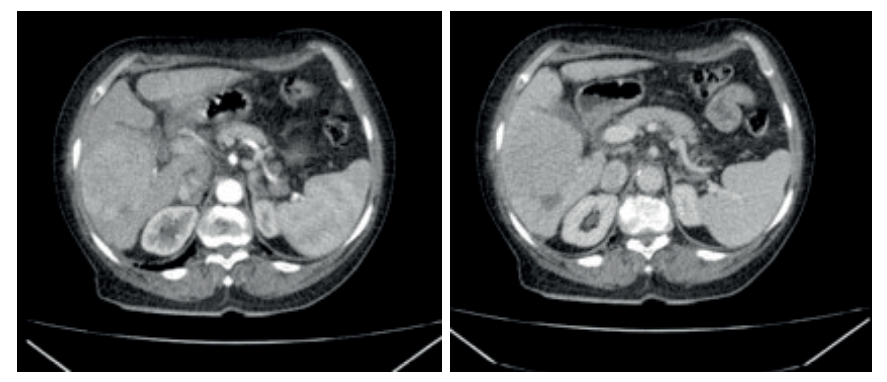

O Padrão Típico (“Washout”):

O fígado recebe sangue majoritariamente da veia porta (75%), mas o CHC, como todo tumor, cria neovasos arteriais.

- Fase Arterial: A lesão brilha intensamente (Hipervascularização), pois recebe sangue da artéria hepática enquanto o resto do fígado ainda está “esperando” o sangue portal.

- Fase Venosa/Portal: O contraste sai rapidamente do tumor (Washout ou lavagem), tornando a lesão hipodensa em relação ao fígado, que agora está brilhando com o contraste portal.

- Pseudocápsula: Realce periférico na fase tardia.